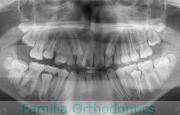

歯並びが悪いのを治したいということで来院されました。前歯の根が短いため、一期治療は最低限拡大するにとどめ、二期治療の時期を待ちました。中学生で再診断したところ、強い叢生(でこぼこ、凹凸、ガタガタ)のため小臼歯を抜歯してマルチブラケット法を行いました。二期の治療期間は約2年、25回程度の通院が必要でした。

短根歯は、移動によって歯根吸収をしたとき、動揺が起こってしまう可能性が高く、ハイリスクな歯です。